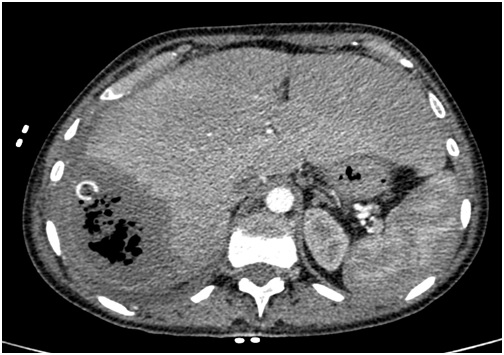

3. рис 2а мскт | |

4. рис 2б | |